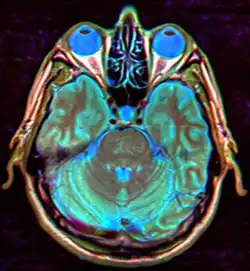

В современных реалиях магнитно-резонансная томография (МРТ) является безопасным и высокочувствительным методом визуализации хиазмально-селлярной области[22][23][24]. Данный метод позволяет проводить исследования в любой плоскости тонкими срезами в 1—1,5 мм, обладает высоким тканевым контрастом, отсутствием артефактов от костных структур черепа.

Для «пустого турецкого седла» характерна триада симптомов:

- наличие цереброспинальной жидкости в полости турецкого седла, о чём свидетельствуют зоны однородного низкоинтенсивного сигнала в режиме T1w и высокоинтенсивного сигнала в режиме T2w, гипофиз при этом деформирован, имеет форму серпа или полулуния толщиной до 2—4 мм, ткань его изоинтенсивна белому веществу мозга, воронка, как правило, расположена центрально;

- асимметричное пролабирование супраселлярной цистерны в полость седла, смещении воронки кпереди, кзади или латерально;

- истончение и удлинение воронки гипофиза.

Помимо основных изменений в параселлярной области МРТ позволяет выявить косвенные признаки внутричерепной гипертензии (расширение желудочков и ликворосодержащих пространств), сопутствующие этой патологии. Разные авторы приводят данные о почти 100 % чувствительности МРТ в диагностике синдрома «пустого» турецкого седла[20][22][23][33].